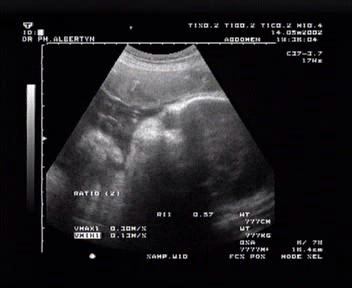

Mariken Face to Face. May 14th

The image is a bit unclear, but believe me. Parents to be get a real kick from seeing this. You get a better idea of what I'm talking about by checking out the latest addition to the 'video page'.